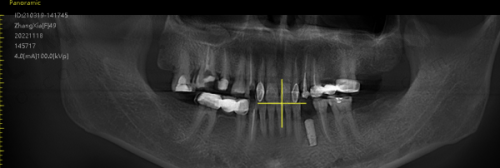

松动后更忌讳拖延!哪怕只是轻微晃动,也要立刻联系种牙医生。医生会用X光片看骨头情况,用专用工具检查螺丝松紧——如果是牙冠松动,当场就能拧紧或换个新牙冠,花几百块半小时搞定;但如果是种植体松动,拖到骨头重度吸收,可能就要“拔了重种”,既花钱又遭罪。北京极简口腔的熊靖宇医生提醒:“去年有个患者拖了3个月才来,种植体周围骨头吸收了2毫米,只能取出后植骨,多花了1万多!”

2. 看技术:数字化种植更精细,减少松动风险

传统种牙靠医生手感,容易位置不准;而数字化种植用3D导板,就像“卫星导航”,误差小于0.1毫米,能避开神经和血管,让种植体和骨头理想结合。极简口腔总院有自己的义齿工厂,牙冠和种植体能精细匹配,咬合力更均匀,松动率比传统方法低60%!